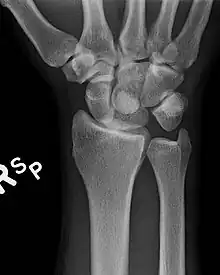

An AP Xray showing a lunate dislocation